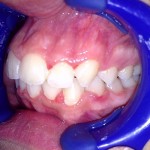

Este é um caso mais simples de se fazer e com um valor (custo-benefício) bastante cómodo.São somente 4 implantes na arcada inferior suportando uma barra sobre a qual será transferido em parte o esforço mastigatório. É confeccionada em RESINA como uma prótese total convencional.